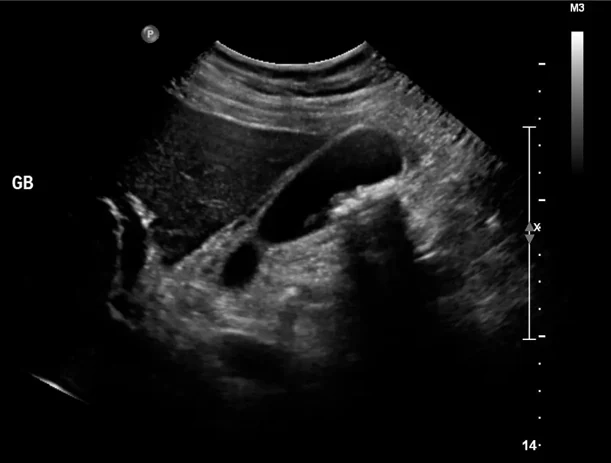

Η διάγνωση της χολολιθίασης γίνεται με την κλινική εξέταση και κυρίως με υπερηχογράφημα κοιλίας. Σε περιπτώσεις που υπάρχει σοβαρή φλεγμονή μπορεί να επηρεαστούν και οι εξετάσεις αίματος του ασθενή.